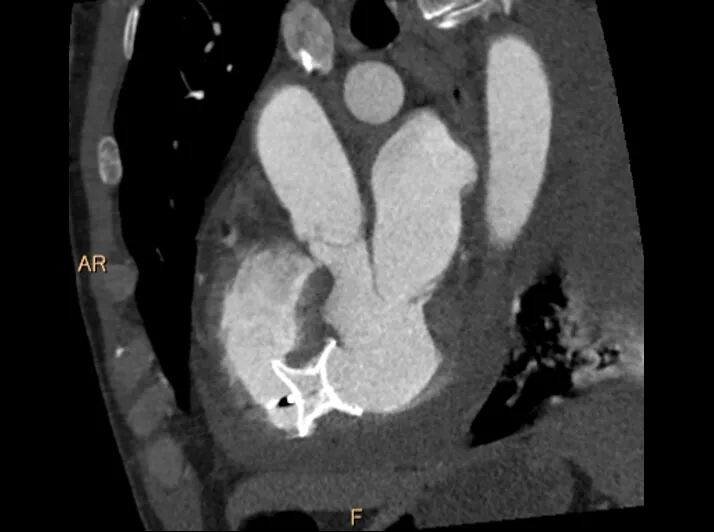

胸痛中心急救电话 17785233019 近年来,贵州航天医院各科室紧跟医学前沿,不断强技术、补短板,大力开展新技术、新项目,完成了许多高精尖、高难度、本地区“首例”的技术,填补了医院医疗技术空白,满足了群众日益增长的医疗需求。 本期,我们将为大家带来心血管内科特色技术——急性心肌梗死伴发室间隔穿孔微创介入封堵术(贵州省内可独立完成此项手术的医院屈指可数)。 案例分享 近期,一名面色苍白、大汗淋漓的患者因急性胸痛被紧急送往我院急诊科,当时患者还伴发严重的急性心衰和心源性休克,病情十分危重,我院急诊科和心血管内科团队当即为患者进行心电图和心脏彩超检查,并在最短时间内得出检查结果,心电图提示:急性下壁ST段抬高型心肌梗塞,心脏彩超提示:急性心肌梗死引发室间隔穿孔。抢救团队争分夺秒,为患者紧急实施了冠脉造影及支架植入治疗,成功稳定了患者的生命体征。 然而,急性心肌梗死引发的室间隔穿孔是一个极为棘手的问题,心血管内科深知开展此例手术的风险性,对此高度重视,立即组织超声科、麻醉科、医学影像科、心脏外科、介入手术室、重症医学科等科室进行多学科讨论(MDT),并在各科室的配合下开展急性心肌梗死伴发室间隔穿孔微创介入封堵术。 考虑患者手术风险大,疼痛刺激可能会加重交感兴奋再次诱发恶性心律失常风险,心血管内科团队在全麻下进行室间隔穿孔封堵治疗,通过穿刺右股静脉、右股动脉,常规行冠脉造影复查冠脉支架通畅,未见狭窄及血栓;又通过DSA进行左心室造影,再次评估室间隔缺损大小,最后成功为患者封堵室间隔穿孔,术后患者病情平稳,住院观察5天后顺利出院。 急性心肌梗死伴发室间隔穿孔这类病例,自然病程8周内的死亡率高达75%,24小时内死亡率也高达25%,此类手术难度系数相当大且死亡率极高。该例患者的及时、成功救治,展现出我院多学科在应对急危重症诊疗工作时所具备的强大实力,更凸显出我院在疑难重症诊治方面的责任与担当。 什么是急性心肌梗死伴发室间隔穿孔 急性心肌梗死后室间隔穿孔(ventricular septal rupture,VSR)是心肌梗死后严重但可以治疗的机械并发症。由于急性心肌梗死后室间隔发生缺血并出现破裂导致的继发性室间隔缺损。 急性心肌梗死伴发室间隔穿孔微创介入封堵术原理 急性心肌梗死伴发室间隔穿孔微创介入封堵术属于外科手术,是利用室间隔穿孔封堵器(哑铃状,左右两边各有一个圆盘,腰呈圆柱体)进行手术,封堵器腰部在释放前收入导管中,导管通过血管到达心房后,放入缺损的位置,在X光机和超声双重定位下,打开封堵器左室盘堵住缺损,再释放右室盘,将室间隔缺损夹在两个圆盘中间,实现对缺损的封堵。 急性心肌梗死伴发室间隔穿孔微创介入封堵术优势 创伤小,痛苦少,疗效迅速,患者普遍易于接受。 贵州航天医院心血管内科 专家团队 姜黔峰 国务院政府特殊 津贴专家 二级教授 博士研究生导师 医学博士 学科带头人 主任医师 贵州省千层次人才,遵义市15851二层次人才。中国胸痛中心执委会委员,国家放射与治疗临床研究中心“国家胸痛中心专家委员会"副主席,中国医疗保健国际交流促进会第二届高血压分会委员,中国医师协会全国高血压专业委员会第一届青年委员,中华老年医学学会心血管分会委员,中国高血压联盟第六届理事会理事,亚太心脏联盟结构性心脏病第一届委员会委员,贵州省中西医结合学会心血管病分会副主委,中华医学会贵州省心脏起搏与电生理分会常委,中华医学会贵州省老年医学分会常委。完成多项省、市级科研课题,主持国家自然科学基金1项。已在国内外期刊发表学术论文100余篇。 临床擅长:高血压、冠心病、心衰的诊治及心血管疾病的介入治疗,尤其擅长先天性心脏病微创介入治疗,已成功完成介入手术治疗2000余例 沈万贵 心血管内科主任 副主任医师 专业擅长:从事临床工作约33年,对冠心病,高血压病,各种心肌病等疾病的诊治以及内科疑难杂症疾病的诊疗具有丰富诊疗经验,累计实施冠心病、外周血管等疾病的介入手术诊疗过万例。擅长于冠脉复杂病变的介入手术治疗、肾动脉狭窄介入手术、下肢深静脉血栓的介入手术治疗。 贵州省医学会心血管病分会常务委员、贵州省心脏病康复医学会常务委员,遵义市医学会心血管病分会副主任委员,西南高血压病管理委员会常务理事,贵州省冠心病组委员;发表学术论文20余篇。 张羽坤 心血管内科 主任医师 专业擅长:具备心血管疾病心律失常介入(导管消融及植入器械)国家级手术资质,参与各类心脏介入手术6000余例。以第一作者在国内核心期刊发表医学论文10余篇,主持市级科研项目1项。 硕士研究生,曾先后前往贵州省人民医院、国家心脏中心北京阜外心血管病医院学习深造(2017年11月至2018年11月参加第二期黔医人才计划并获得优秀学员称号),2022年获得贵州省“第二届最美劳动者”称号。 中国医疗保健国际交流促进会心律与心电分会第三届委员,中国老年医学学会心血管病分会第二届委员会基层委员,贵州省心电生理与起搏分会委员,贵州省中西医结合学会心血管专业委员会委员,遵义医学会心血管病学分会常委,遵义市医学会(第六届)理事会理事,遵义市健康科普专家;是遵义医科大学科技学院及遵义医药高等专科学校兼职教师。 李树刚 心血管内科 副主任医师 专业擅长:具备冠心病介入手术治疗资质,对心内科各种常见病、多发病及急性冠脉综合征疾病具有丰富的临床诊治经验,完成各项冠心病介入治疗6000余台。 毕业于遵义医学院临床医学专业,以第一作者在国内核心期刊发表医学论文数篇,主持并结题市级科研项目1项;遵义市医学会心血管病分会委员,遵义市健康科普专家成员。 胡兴丽 心血管内科 副主任医师 专业擅长:对心血管及内分泌相关常见疾病的诊治及抢救工作具有丰富的临床经验,擅长心血管及心律失常的介入手术。 2009年毕业于遵义医学院临床医学专业,临床工作10余年,有外出进修 CCU 学习经历,发表论文数篇。云贵川高血压联盟委员。 杨 菊 心血管内科 副主任医师 临床擅长:具备心血管疾病冠脉介入手术资质,参与各类冠心病介入手术3000余例。 医学硕士,遵义市医学会心血管病分会委员,多次获得“优秀党员”、“优秀帮扶对象”、“优秀带教老师”等荣誉称号,遵义医药高等专科学校及遵义医科大学科技学院兼职教师;以第一作者在国内核心期刊发表医学论文数篇,主持并结题市级科研项目1项。 张 禹 心血管内科 副主任医师 临床擅长:熟练掌握冠心病、心律失常、高血压、心力衰竭、风湿性心脏病、扩心病等心血管疾病诊治,以及急、危、重症病人的救治。 2017年在重庆第三军医大学新桥医院心内科进修学习,2018年贵州省人民医院进修心律失常介入治疗,取到心血管疾病心律失常介入(导管消融)国家级手术资质,参与冠脉介入、射频消融、起搏器置入等心内科介入手术4000余例;是遵义市医学会心血管病分会委员。 李茂春 心血管内科 副主任医师 临床擅长:1995年毕业于遵义医学院临床医学系,从事临床工作28年,熟练掌握高血压、冠心病等心血管疾病的诊治及危急重症患者的救治,擅长糖尿病、甲状腺功能亢进、代谢综合征等内分泌代谢性疾病的诊治,在多年的临床工作中对内分泌代谢疾病、心血管疾病的诊治中积累了丰富临床的经验。 贵州省医学会内分泌暨糖尿病学分会第七届委员会甲状腺学组组员,遵义市内分泌暨糖尿病学分会第一届委员会常务委员,贵州省康复医学会骨内科专业委员会遵义地区分会常务委员。多年来在省内外期刊发表论文数十篇。 刘忠凤 心血管内科 副主任医师 临床擅长:对结构性心脏病超声心动图的判读及解析、结构性心脏病的诊疗有丰富的临床诊疗经验;擅长心血管常见多发病及难治性心衰的诊治、恶性心律失常的抢救。 遵义市医学会心血管病分会委员,遵义市医学会内分泌暨糖尿病分会委员,遵义市医学会骨质疏松暨骨矿盐疾病学分会委员;曾前往贵州省人民医院超声心动图室、四川大学华西医院超声科进修学习超声图;发表省级期刊数篇,参与结构性心脏病术中超声指导。 贵州航天医院心血管内科简介 • ✦ 基本情况 ✦ • 贵州航天医院心血管内科编制床位60张,配置了29台24小时动态心电图、110台24小时动态血压、心脏除颤仪、监护仪、输液泵、微量注射液,同步12导联、18导联心电图机、临时心脏起搏器、床旁血糖仪、主动脉内球囊反搏、食道超声、血管内超声诊断仪及DSA心血管诊疗等。 • ✦ 学科、专科建设 ✦ • 近年来成功获批胸痛中心、房颤中心、儿童先天性心脏病定点救治单位授牌;是遵义市临床重点专科、远程心电示范中心、高血压慢病管理示范中心。 • ✦ 诊疗范围 ✦ • 开展了急诊冠脉介入诊疗,冠脉复杂病变介入术、冠状动脉斑块旋磨术、心脏再同步治疗起搏器植入术、心脏再同步治疗除颤器植入术、射频消融术【心房颤动(导管消融、冷冻消融)、心房扑动、房性心动过速、室性心动过速、室性早搏】、结构性心脏病介入治疗【房间隔缺损(卵圆孔未闭)封堵术、室间隔缺损封堵术、动脉导管未闭封堵术、冠状动脉瘘封堵术、左心耳封堵术等】、临时起搏器植入术、常规永久起搏器植入术(双腔、单腔)、下肢动静脉造影术、下腔静脉滤器植入及取出术、自主肾上腺静脉采血、颈动脉支架植入术、外周动脉支架植入术、肾动脉支架植入术等,积极开展冠脉内超声检查、FFR、OCT、心脏射频三维手术、房颤一站式治疗(房颤射频消融术+左心耳封堵术)、主动脉瓣介入术等,并邀请院外专家指导成功开展腹主动脉支架植入术。 • ✦ 咨询信息 ✦ • 门 诊 地 址:贵州航天医院呼吸综合楼1楼013诊室。 住院病区 地 址:贵州航天医院外科综合楼9楼 咨询电话 护士站:28611793 医生办公室:27677832